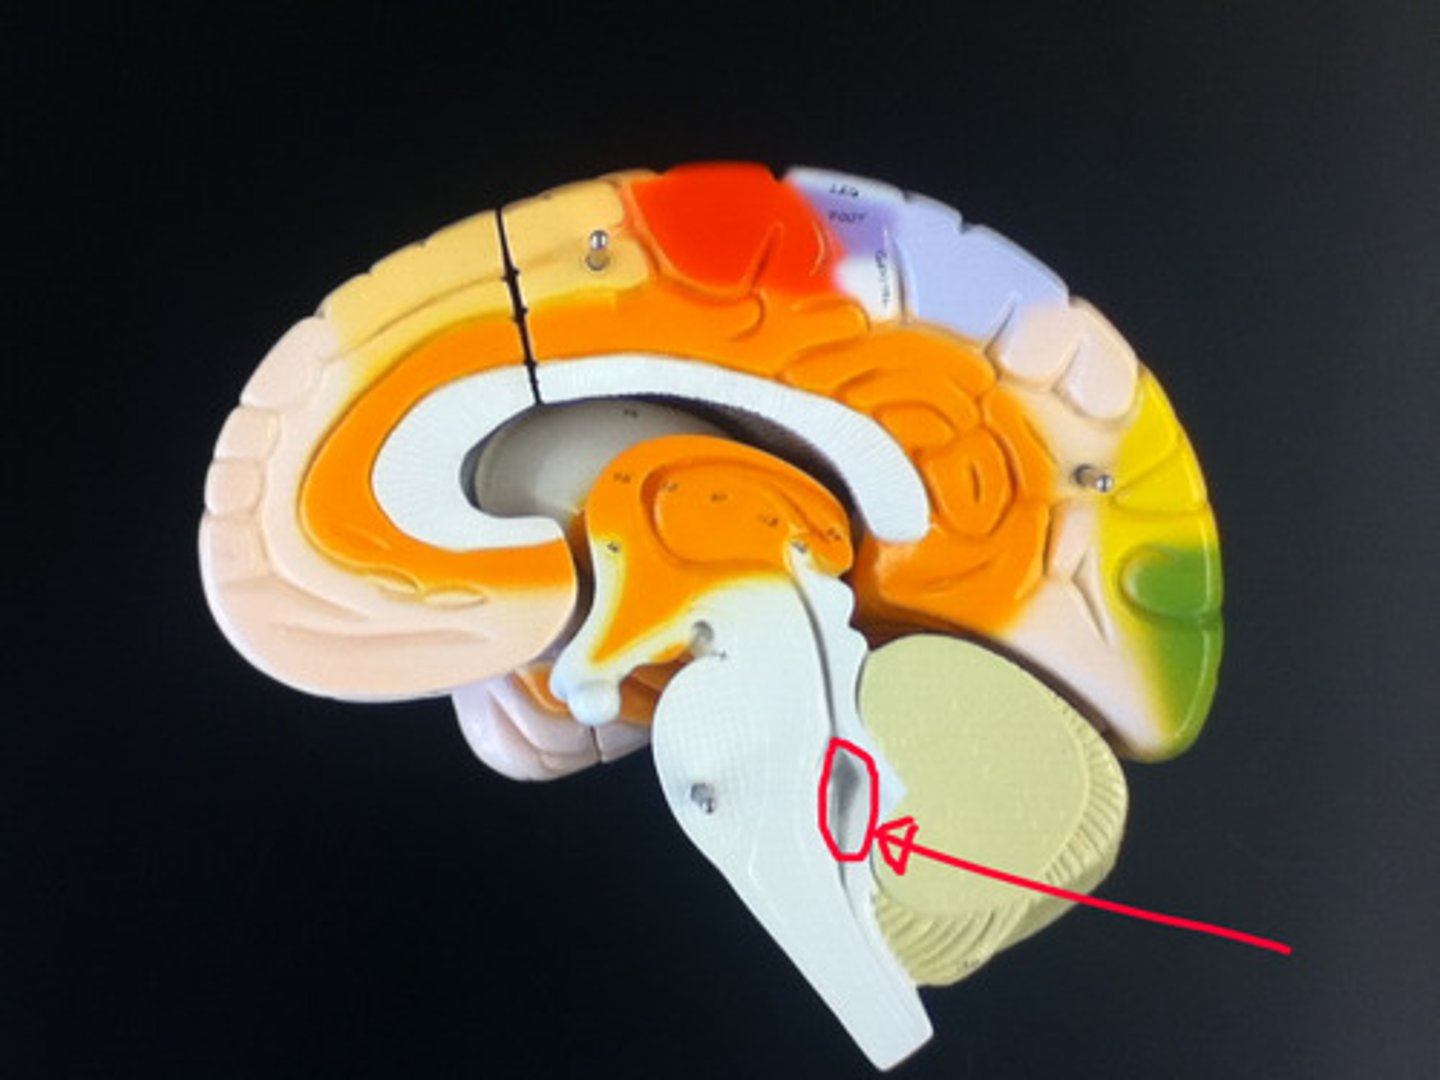

MIdsagittal View of brain

Lateral Ventricle

Third Ventricle

Cerebral Aqueduct

Forth Ventricle

Corpus Callosum

Fornix

Thalamus

Pineal Gland

Superior Colliculi

Inferior Colliculi

Midbrain

Hypothalamus

Cerebral Cortex Gray Matter (nerve cell bodies)

White Matter (myelinated nerve fibers)